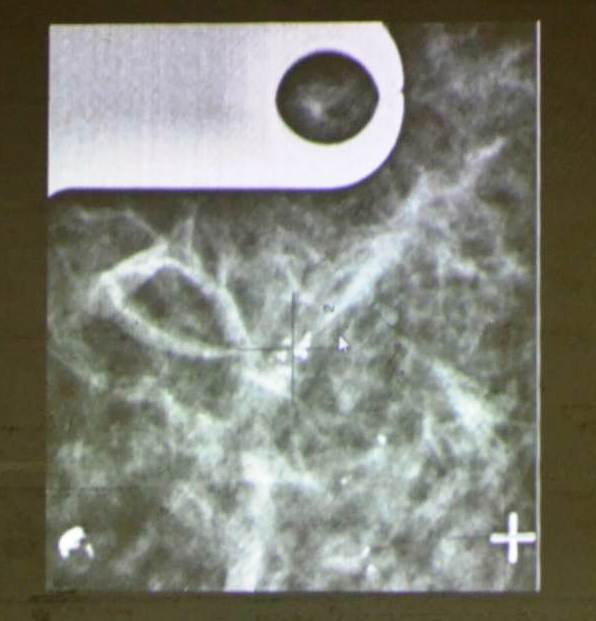

Ομιλητές ήταν ο Γιώργος Κυρόπουλος, ακτινολόγος – εξειδικευμένος στις παθήσεις μαστού και ο Χρήστος Βρέκας, χειρουργός μαστού.

- Δείτε εικόνες και βίντεο από την σημαντική εκδήλωση – ενημέρωση: